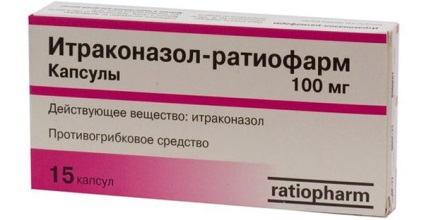

Orvosi gyakorlatban kezelésére ótvar, a következő típusú tablettát:

Ezeket a gyógyszereket venni mindaddig, amíg a tartály terményt a fejbőr nem lesz negatív. A legtöbb esetben ez történik belül 1 vagy 2 hónap. Ha ótvar kíséri bakteriális fertőzés, antibiotikumot adunk a kezelést.